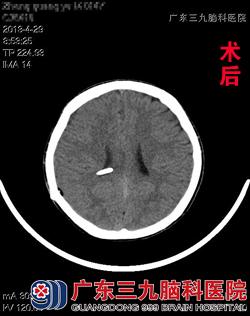

入院后完善相关检查,明确脑脊液性状,确定手术适应症后,小郑在全麻下接受了脑室腹腔分流术,术程顺利,术后予以抗炎、止血、营养支持、暂禁食水等处理。术后10天康复出院。www.999brain.com